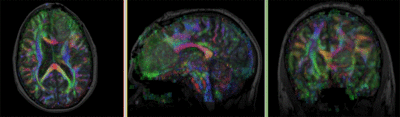

DTI aligned with T1